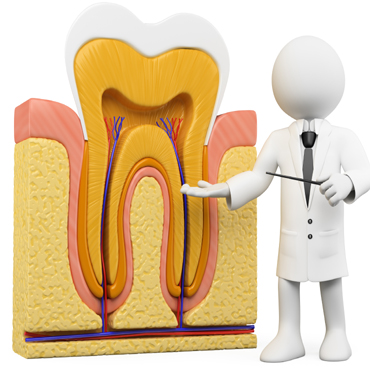

Shagun Dental Care in Lucknow offers a host of treatments and cures for a wide range of dental ailments faced by the patients. Few of the dental procedures they offer range from inducing fillings and repairs in the tooth, undertaking root canal surgeries, applying crowns (caps), bridges and implants, teeth whitening as well as extractions (surgical removal) of cavities/milky /disfigured/wisdom teeth.